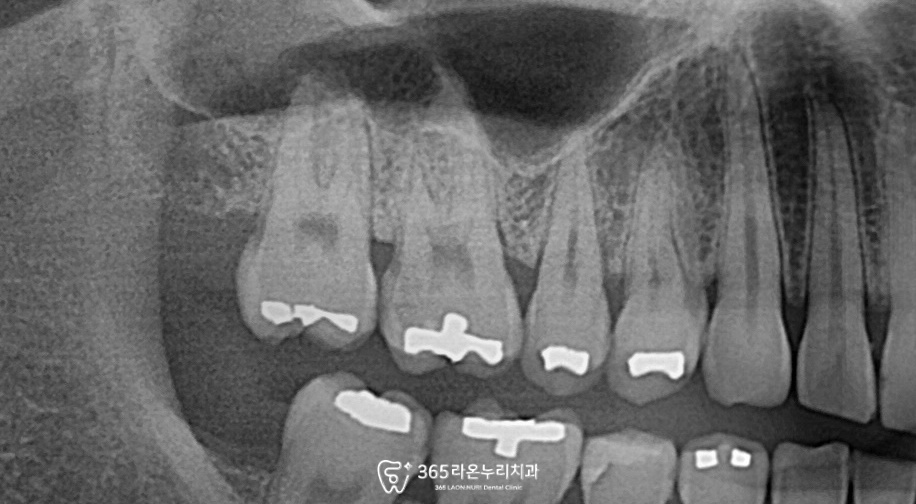

증상이 있는 치아를 살펴보면

아말감로 수복된 부위를

확인했습니다.

아말감 하방으로 거무스름하게

비치는 것이 관찰됩니다.

이러한 경우 대부분

이차우식증 이 발생되었을

가능성이 매우 높습니다.

신장동 치과 에서는

내부를 확인하기 위하여

엑스레이를 촬영하였습니다.

2025. 03. 20

방사선 불투과성 재료인

아말감 밑으로 충치가

진행된 것을 확인됩니다.